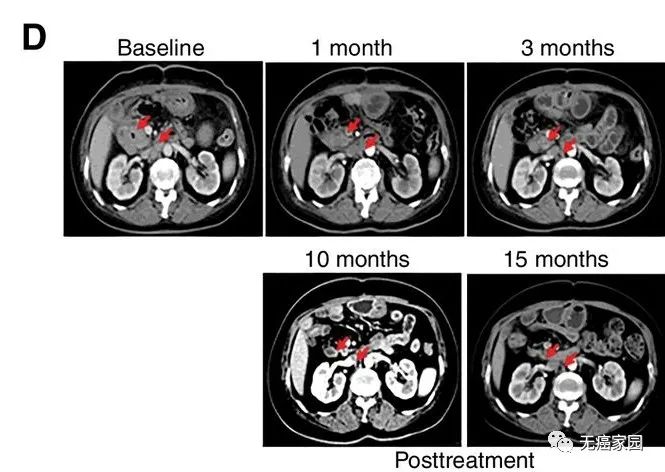

此次纳入的患者均为EGFR强阳性(>50%的癌细胞表达EGFR)的不可切除的胆道系统恶性肿瘤患者,共纳入19例患者,包括胆管癌14例,胆囊癌5例。

研究结果显示,17例患者可评估,其中1例胆管癌患者的肿瘤完全消失,截止到目前疗效已经保持了22个月,尚未发现疾病复发。10例患者疾病稳定,疗效保持2.5~15.5个月,中位无进展生存期为4个月。

CART-RGFR细胞治疗之前和1、3、10和15个月患者1的CT扫描图像。红色箭头表示原发肿瘤和腹膜后淋巴结转移。

在研究中有10例患者在化疗预处理中出现3~4级的副作用,经积极处理均可恢复正常。